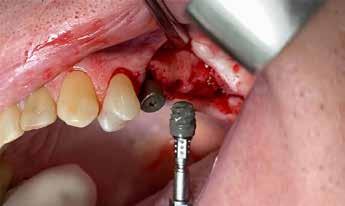

A részleges extrakció befejezése után következhet az implantátumágy preparálása a gyártó utasításai szerint (6.

6. kép: Implantátum-ágy preparáció. 7. a–b. képek: Implantátum behelyezés. 8. kép: A behelyezett implantátum. 10. a–b képek: Azonnali ideiglenes korona készítése. 9. kép: Megfelelő primer stabilitás.

A 2.5-ös fog mentén periotómot haszáltunk, hogy átvágjuk a periodontális rostokat, így a fogat kilazítottuk, hogy ezzel is csökkenthessük a fogó által végzendő laterális mozgások szükségességét, illetve hogy a környező csontot is a legnagyobb mértékben megőrizzük. Nem volt elég csont (anélkül, hogy perforálnánk az arcüreg alapját) ahhoz, hogy abban stabilizáljuk az implantátumot, úgy döntöttünk, hogy behelyezünk egy ∅ 5.0 x 12 mm-es Straumann® BLX implantátumot közvetlenül az alveolusba, előfúrás nélkül. Az implantátum menetkialakítása lehetővé tette, hogy a kézidarabbal behajtva, 25 Ncm-es nyomatékot érjünk el, majd racsnis nyomatékkulcs segítségével juttattuk a végső pozíciójába, 80 Ncm-es behajtási nyomatékot mérve (3. és 4. ábrák).